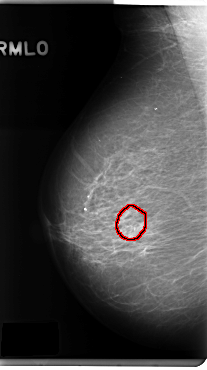

C_0285_1.RIGHT_MLO

RIGHT_MLO LINES 4800 PIXELS_PER_LINE 2688 BITS_PER_PIXEL 12 RESOLUTION 50 OVERLAY

FILE: C_0285_1.RIGHT_MLO.OVERLAY

TOTAL_ABNORMALITIES 1

ABNORMALITY 1

LESION_TYPE CALCIFICATION TYPE FINE_LINEAR_BRANCHING DISTRIBUTION CLUSTERED

ASSESSMENT 4

SUBTLETY 5

PATHOLOGY BENIGN

TOTAL_OUTLINES 1

BOUNDARY